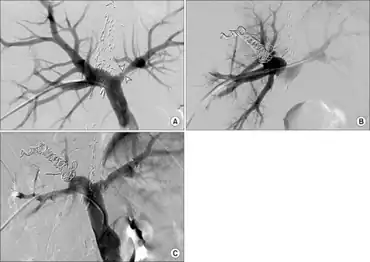

| L-Citrulline | |